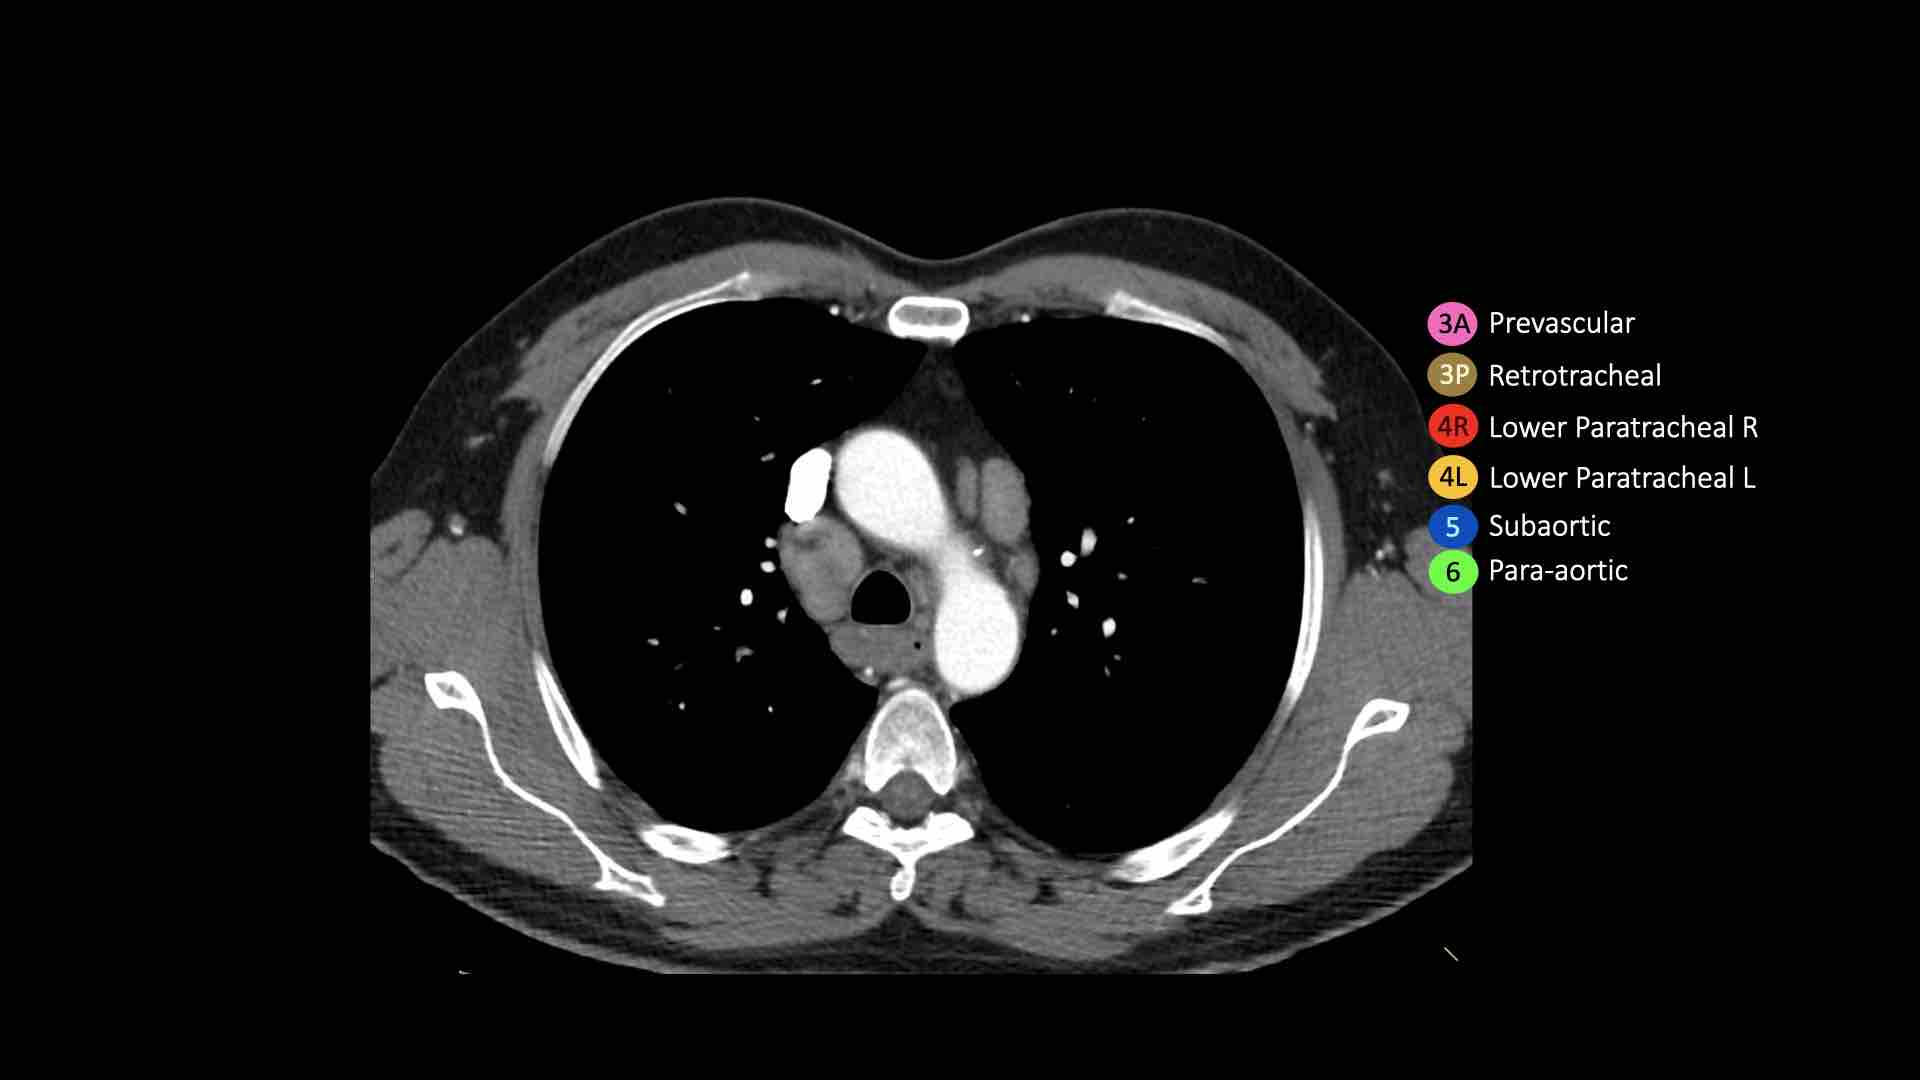

3A.Trước mạch máu

Các hạch này không tiếp giáp với khí quản như các hạch ở nhóm 2, mà nằm ở phía trước các mạch máu.

3P.Trước cột sống

Các hạch không tiếp giáp với khí quản như các hạch ở nhóm 2, mà nằm sau thực quản, tức là ở vị trí trước cột sống.

4R.Cạnh khí quản dưới

Từ điểm giao nhau giữa bờ dưới tĩnh mạch vô danh (tĩnh mạch tay đầu trái) với khí quản đến bờ dưới tĩnh mạch đơn.

Hạch nhóm 4R trải dài từ bờ bên phải đến bờ bên trái của khí quản.

4L.Cạnh khí quản dưới

Từ bờ trên của quai động mạch chủ đến bờ trên của động mạch phổi trái.

Hạch động mạch chủ nhóm 5-6

5. Dưới động mạch chủ

Các hạch này nằm trong cửa sổ phế động mạch (AP window), ở phía ngoài dây chằng động mạch.

Các hạch này không nằm giữa động mạch chủ và thân động mạch phổi mà nằm ở phía ngoài các mạch máu này.

6. Cạnh động mạch chủ

Đây là các hạch của động mạch chủ lên hoặc hạch cơ hoành, nằm ở phía trước và bên của động mạch chủ lên và quai động mạch chủ.

3. Hạch trước mạch máu và trước cột sống

Hạch nhóm 3 không nằm kề khí quản như hạch nhóm 2.

Chúng có thể là:

3A nằm phía trước các mạch máu, hoặc

3B nằm phía sau thực quản, vốn nằm ở vị trí trước cột sống.

Hạch nhóm 3 không thể tiếp cận bằng nội soi trung thất.

Hạch 3P có thể tiếp cận bằng siêu âm nội soi (EUS).

Bên trái là hạch 3A nằm trong khoang trước mạch máu.

Lưu ý cũng có các hạch cạnh khí quản dưới bên phải, tức là hạch nhóm 4R.

4R. Hạch cạnh khí quản dưới bên phải

Ranh giới trên: giao điểm của bờ dưới tĩnh mạch vô danh (tĩnh mạch tay đầu trái) với khí quản.

Ranh giới dưới: bờ dưới tĩnh mạch đơn.

Hạch nhóm 4R trải dài đến bờ bên trái của khí quản.

Bên trái là hạch cạnh khí quản 4R.

Ngoài ra còn có một hạch động mạch chủ nằm bên ngoài quai động mạch chủ, tức là hạch nhóm 6.

4L. Hạch cạnh khí quản dưới bên trái

Hạch nhóm 4L là các hạch cạnh khí quản dưới nằm bên trái bờ trái của khí quản, giữa đường nằm ngang tiếp tuyến với bờ trên quai động mạch chủ và đường tiếp tuyến với bờ trên động mạch phổi trái.

Nhóm này bao gồm các hạch cạnh khí quản nằm ở phía trong dây chằng động mạch.

Hạch nhóm 5 (cửa sổ phế động mạch) nằm ở phía ngoài dây chằng động mạch.

Bên trái là hình ảnh ngay trên mức thân động mạch phổi, cho thấy các hạch cạnh khí quản dưới bên trái và bên phải.

Ngoài ra còn có các hạch nhóm 3 và nhóm 5.

Bên trái là hình ảnh ở mức phần dưới khí quản, ngay trên carina.

Bên trái khí quản là các hạch 4L.

Lưu ý rằng các hạch 4L này nằm giữa thân động mạch phổi và động mạch chủ, nhưng không nằm trong cửa sổ phế động mạch, vì chúng nằm ở phía trong dây chằng động mạch.

Hạch nằm bên ngoài thân động mạch phổi là hạch nhóm 5.

5. Hạch dưới động mạch chủ

Hạch dưới động mạch chủ hay hạch cửa sổ phế động mạch nằm ở phía ngoài dây chằng động mạch hoặc động mạch chủ hoặc động mạch phổi trái, ở đoạn gần trước nhánh đầu tiên của động mạch phổi trái, và nằm trong bao màng phổi trung thất.

6. Hạch cạnh động mạch chủ

Hạch cạnh động mạch chủ (động mạch chủ lên hoặc cơ hoành) nằm ở phía trước và bên ngoài động mạch chủ lên và quai động mạch chủ, từ bờ trên đến bờ dưới của quai động mạch chủ.